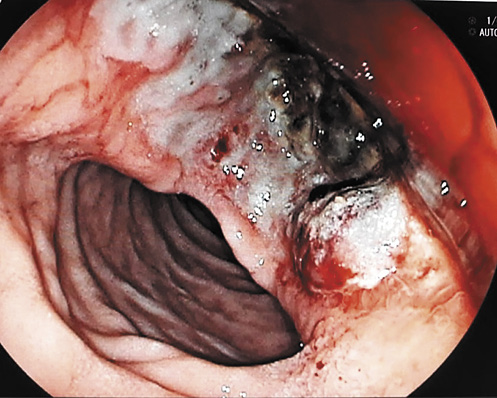

An esophagogastroduodenoscopy showed a giant ulcer in the duodenal bulb 5 cm in diameter, which presented a tightly adherent blood clot, a necrotic base, and a suspect fistulous orifice localized on the posterior wall of the duodenal bulb. In addition, a bulge on the duodenal bulb, suggestive of an extrinsic compression, was noticed (Fig. 1). There was mild diffuse oozing of blood from the lesion. The clot was removed with cold snaring, and bipolar diathermy was applied to the lesion to achieve adequate hemostasis. Biopsy samples from the ulcer edge showed inflammatory slough without fibrosis. A regimen of intravenous omeprazole (80-mg boluses), followed by a continuous infusion of 8 mg/h for 72 h, was initiated, and transfusions of 2 units of packed red blood cells were ordered.

Fig. 1 Esophagogastroduodenoscopy showing a giant ulcer in the duodenal bulb 5 cm in diameter, which presented a tightly adherent blood clot and a necrotic base. There was mild diffuse oozing of blood from the lesion.